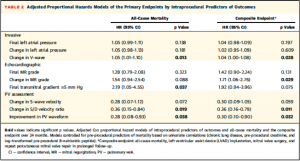

続いて、全死亡、複合エンドポイントに関して術前の慢性肺疾患の有無、血清クレアチニン値、BNP値で調整したProportional hazard modelを用いて単変量解析を行った(Table 2) 。V波の低下は全死亡、複合エンドポイントの両方に関連していた。また、僧帽弁圧較差の上昇は全死亡と関連しており、MR重症度の有無は複合エンドポイントに関連していた。肺静脈波形に関するパラメーター (S波の変化、S/D波の比の変化、PV波形の改善有無)はそれぞれ全死亡、複合エンドポイントの両方に関連していた。

(Table 2)

(Table 2)